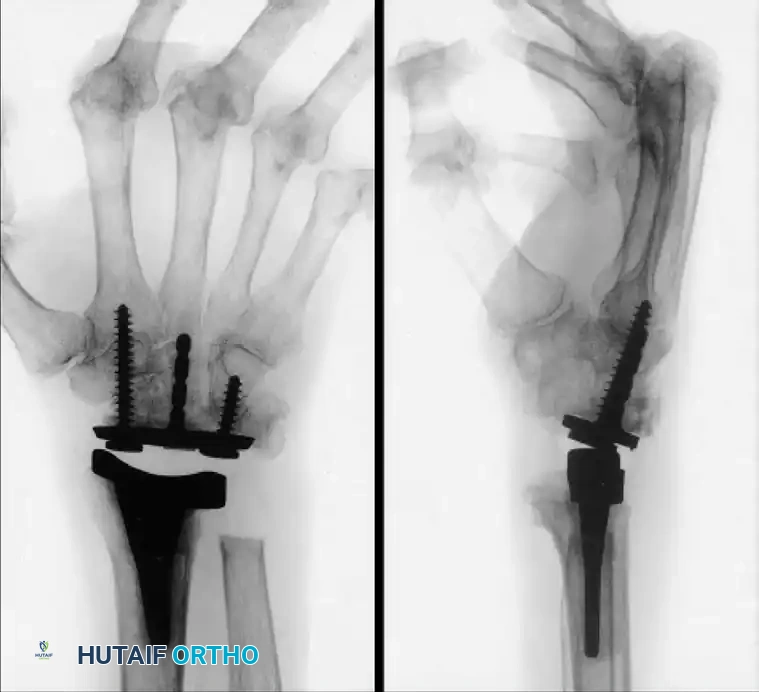

Ulnar subluxation in a 54-year-old woman with rheumatoid arthritis (Left), successfully stabilized and realigned after a radiolunate (Chamay) fusion (Right).

The Radiolunate (Chamay) Fusion:

This procedure is particularly effective for isolated radiolunate arthritis or to halt ulnar slide in the rheumatoid wrist while preserving the midcarpal articulation (capitolunate joint) for flexion and extension.

By fusing only the affected radiocarpal segment, the surgeon maintains the kinematic dart-thrower's motion arc, which is essential for many occupational and daily activities.